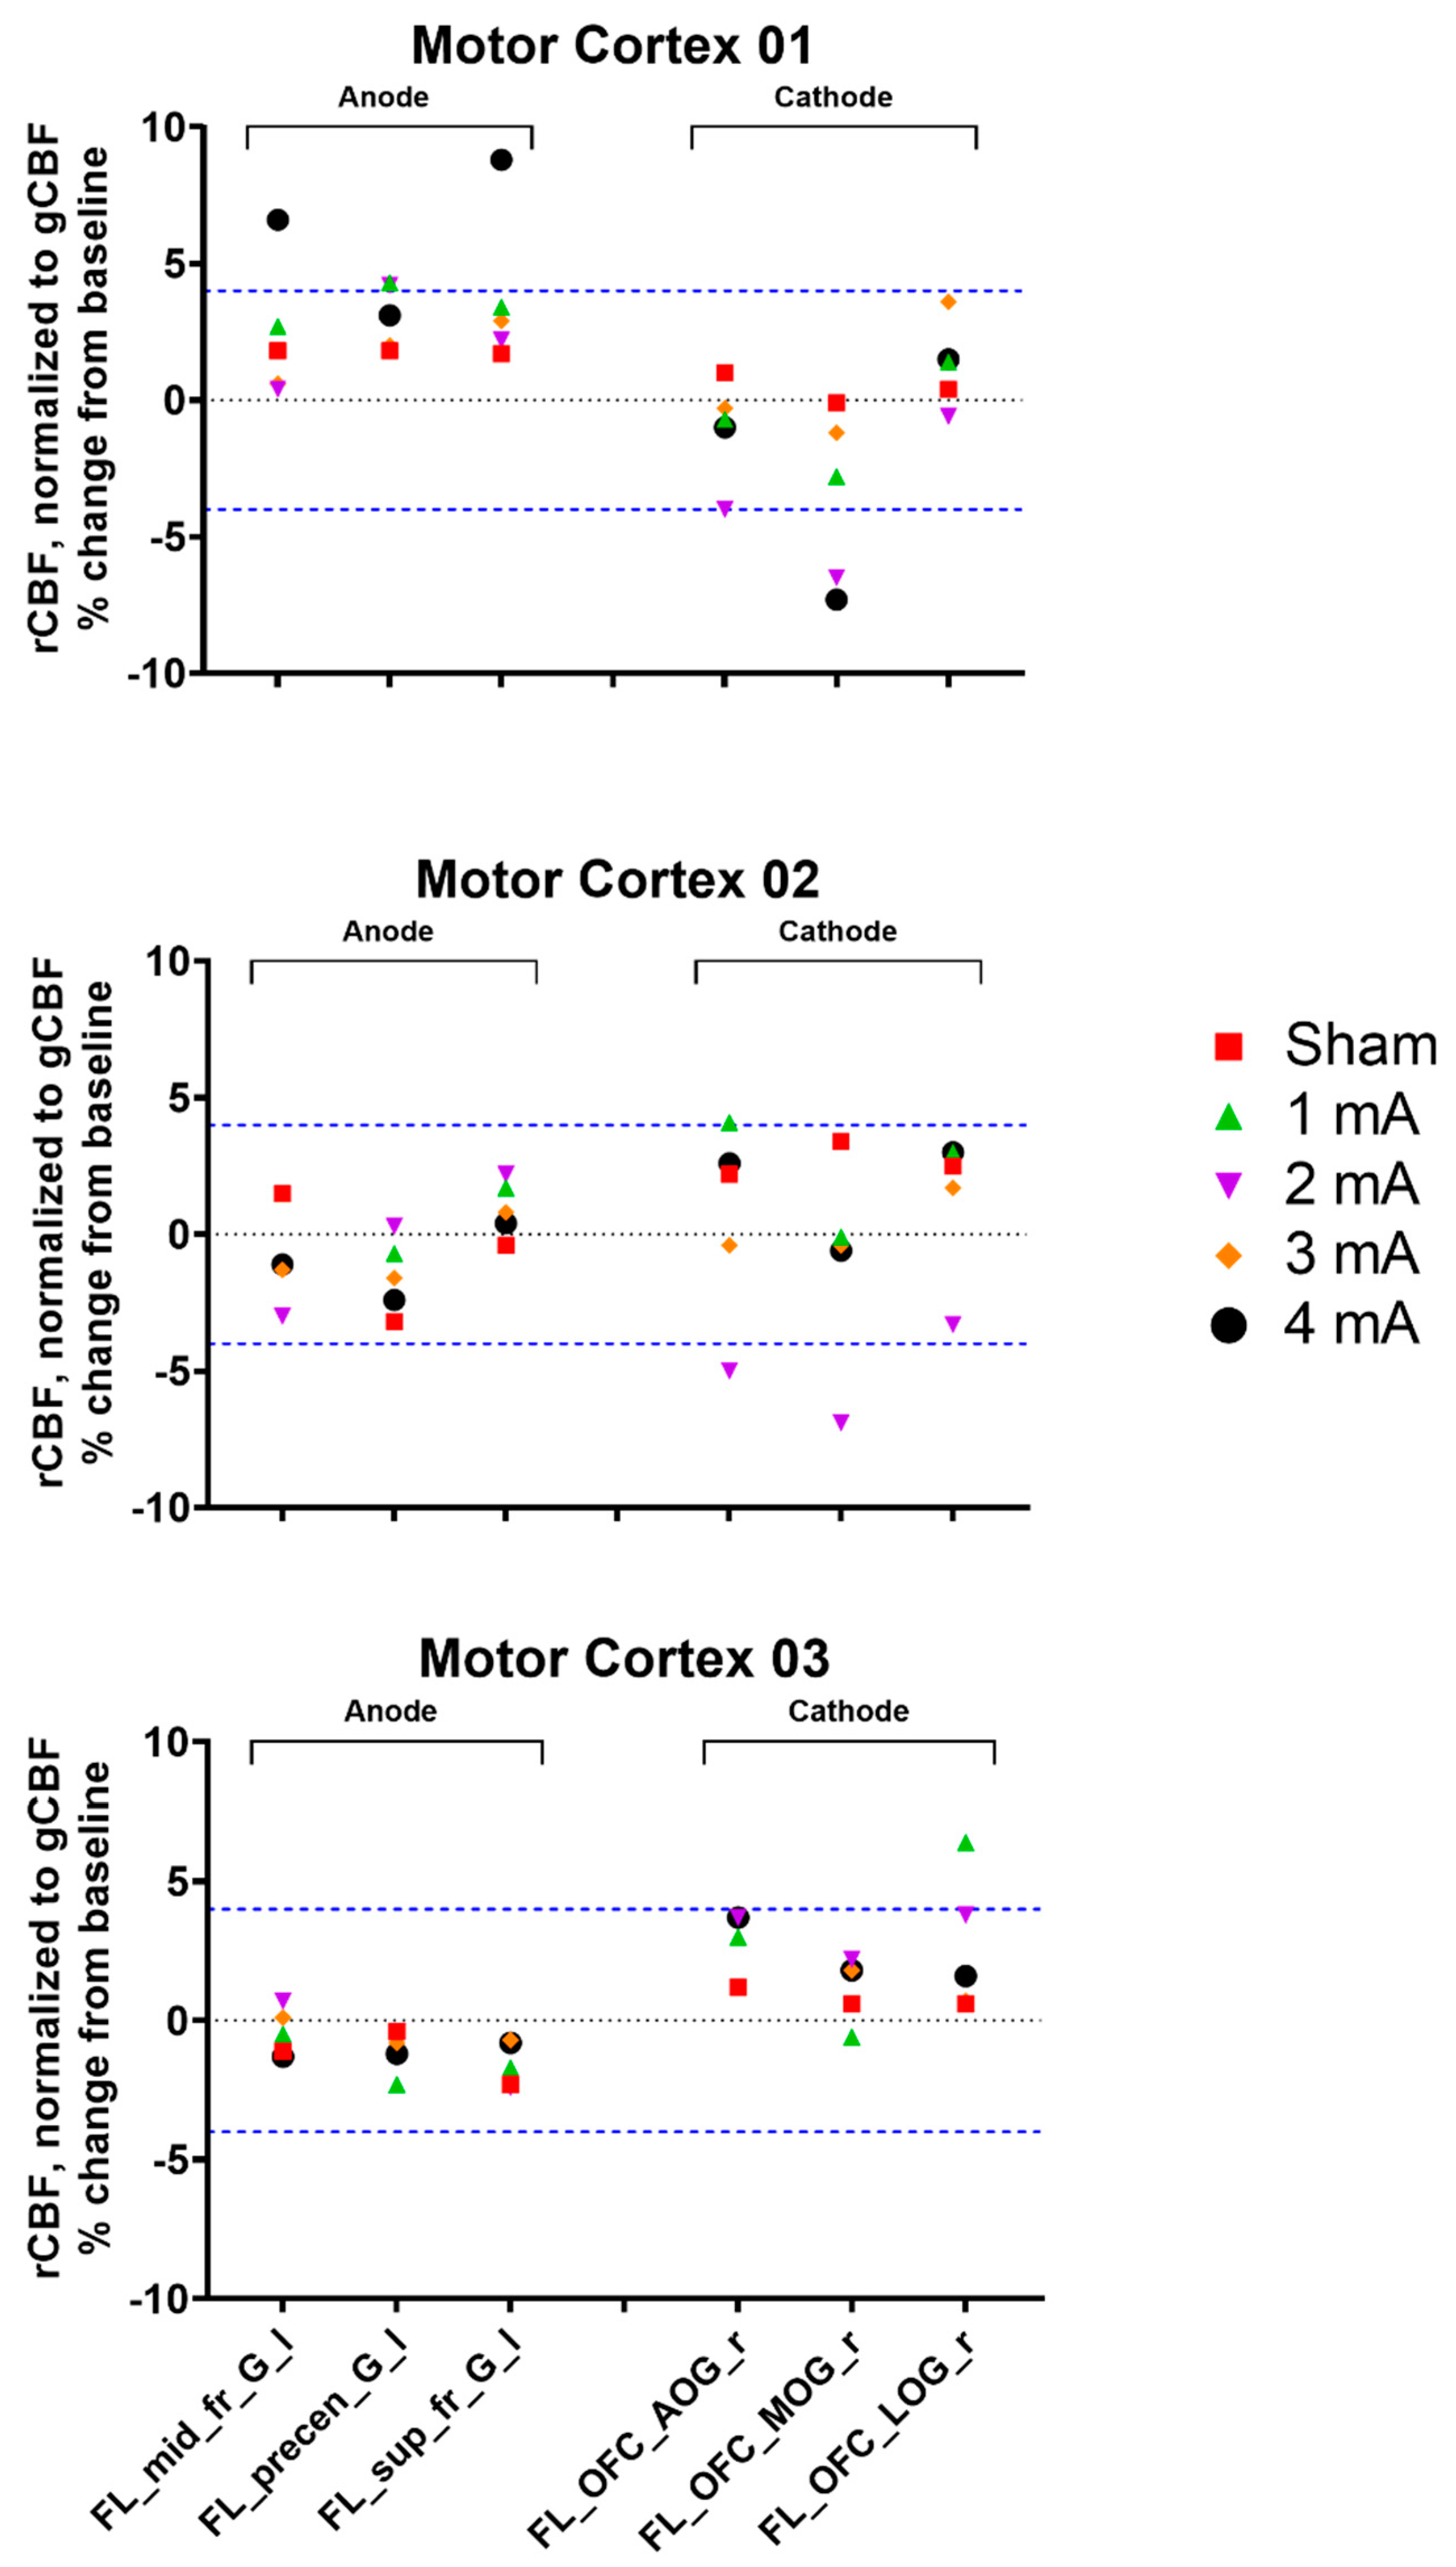

3. Results

3.2. Experiment 2, Primary Motor Cortex